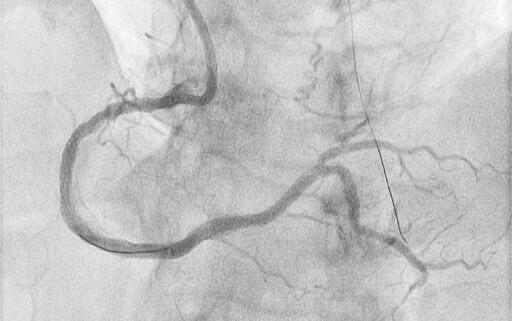

A Convey CLS 4 6F guiding catheter (Boston Scientific) was engaged in the left main coronary artery, and an Amplatz left 1 7F was engaged in the ostium of the RCA. Starting from the antegrade with a Gladius EX guidewire (Asahi) and a Turnpike Spiral microcatheter (Teleflex), a dissection reentry was attempted. Τhe Gladius EX, the Gaia Next 2 (Asahi), the Confianza Pro 12 (Asahi), and the Hornet 14 (Boston Scientific) were used consecutively, passing inside the outer layer of the vessel (adventitia), next to the old stent, and reentering in the distal part of the RCA. In order to reenter the true lumen before the bifurcation, a Stingray balloon (Boston Scientific) was used. A Gaia Next 3 was advanced inside the Stingray, successfully reentering the lumen. Afterwards, balloon inflation was performed throughout the vessel and, finally, 4 stents were deployed with a good angiographic result and Thrombolysis in Myocardial Infarction-III flow (Figures 1 and 2, Videos 1 and 2). The patient was discharged the next day.

Four days later, the patient was admitted to the cardiology department because of exertional dyspnea. Because of the recent revascularization of the RCA, a new coronary angiography was performed. The angiography of the left system revealed no changes, but the RCA unveiled a nimble formation in the proximal part of the stented vessel (Figure 3, Video 3). An intravascular ultrasound was performed, which displayed the double-barrel configuration (Figures 4 and 5, Video 4) and the presence of a thrombus (Figures 6 and 7, Video 5). It was directly stented with an excellent angiographic result (Video 6). Two days postoperative, the patient was asymptomatic and discharged.